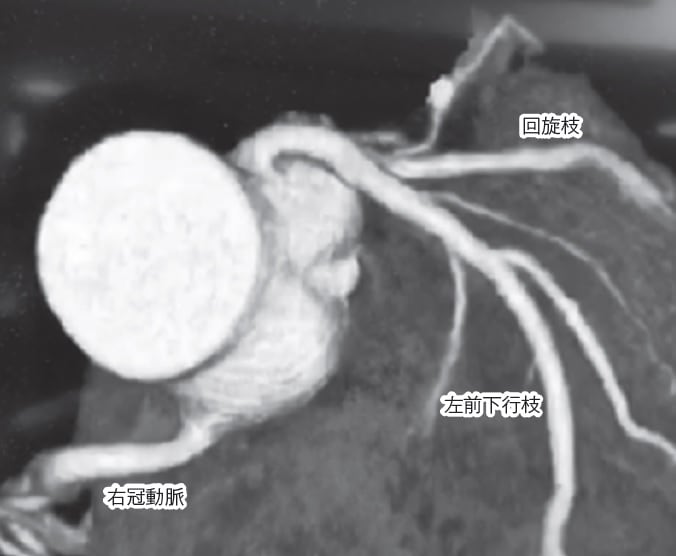

●冠動脈も3Dで検査できるようになった

しかし現在は、バーチャル大腸内視鏡検査で紹介したように、冠動脈の場合も造影剤を点滴しながらCT撮影を行い、そのデータを3D画像に組み立てる「3D‐CT検査」が登場しています。これなら患者さんの身体的負担も少なく、体を傷つけないので合併症のリスクもなくなります。

まさに最新の検査ですから、筆者も興味津々で専門病院を訪れました。筆者のクリニックでは対応できないので、患者として大病院を受診することにしたのです。こうして冠動脈の検査を受けた結果、異常なしというお墨付きをいただきました。それ以来、マラソンも安心して走れるようになったのです。